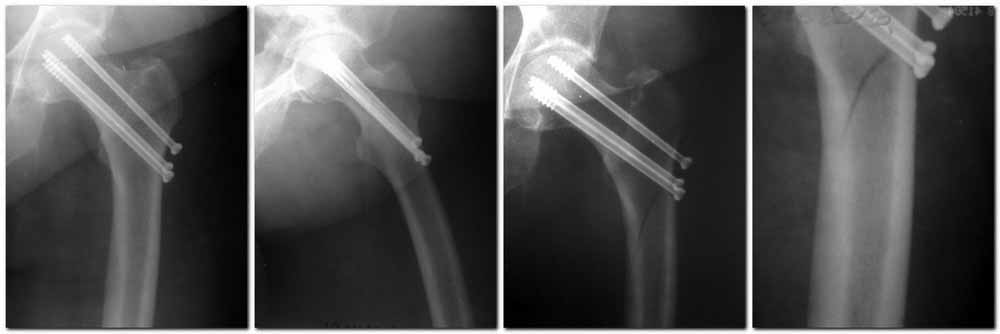

Подвертельный перелом после МОС шейки винтами

Пациентка Ш. 76 лет, 11 дней назад прооперирована по поводу вколоченного субкапитального перелома шейки левой бедренной кости, 3-мя канюлированными винтами. Вчера пациентка упала в палате. И вот результат- подимплантатный подвертельный перелом левой бедренной кости.

Уважаемые коллеги, пожалуйста посоветуйте какой метод дальнейшего лечения предпринять дальше. Соматически пациента повышенного питания, страдает варикозной болезнью нижних конечностей. Из предложенных вариантов коллег - целллокастовая укороченная кокситная повязка, скелетное вытяжение сроком на 40-45 суток - отпали сразу, так как необходимо активизация пациентки. На данный момент рассматриваем следующие варианта реостеосинтеза:(наличие технических возможностей)

1. Длинная Gamma 3 Stryker (с предварительной интраоперационной фиксацией головки спицами). 2. Трохантерный штифт DePuy с 2-мя метафизарными винтами в проксимальном отделе, (также с интраоперационной фиксацией головки спицами.

Очень настораживает стабильность фиксации с проксимальном отделе с связи с выборкой костной ткани ранее находящимися там канюлированными винтами.

Заранее извиняемся за качество и неполное соответствие проекций на R-ммах (R-служба отдельная песня). При интраоперационном ЭОП-контроле винты в аксиальной проекции разнесены по шейке.